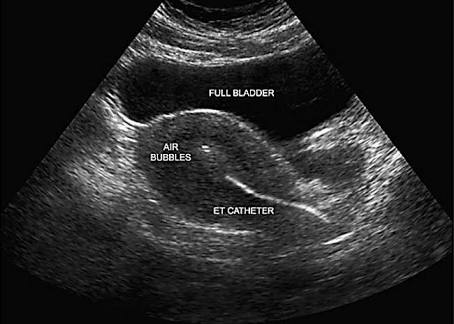

Embryo Transfer